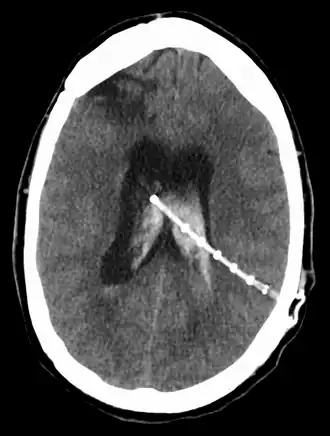

Een ventrikeldrain is een drain of shunt (kunststof afvoerbuisje) in de ventrikels van de hersenen en wordt door een neurochirurg geplaatst in de steriele omgeving van een operatiezaal. De functie van de ventrikeldrain is tweeledig. Enerzijds kan men via deze drain de druk van het hersenvocht meten. Anderzijds kan men, indien nodig, bij overdruk ventrikelvocht draineren (afvoeren) in een recipiënt (zakje, bakje, holte) om zo de hersenen meer ruimte te geven en de druk van het hersenvocht op de hersenen te verminderen. De tip van de ventrikeldrain bevindt zich in de ventrikels, in het midden van de hersenen. Normale menselijke hersenen bevatten vier ventrikels, meestal bevindt een ventrikeldrain zich in de derde en grootste ventrikel.